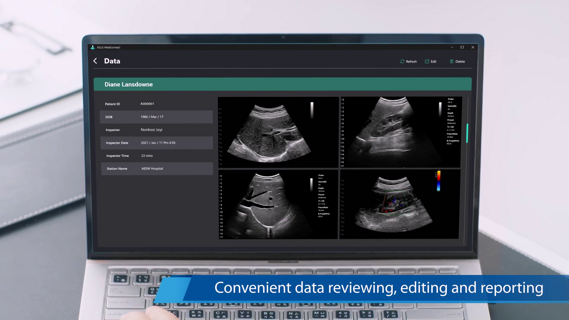

TE Air può essere collegato senza soluzione di continuità al sistema informativo dell'ospedale per migliorare il flusso di lavoro del reparto; i dati anonimizzati vengono archiviati e condivisi per soddisfare le esigenze di insegnamento, formazione, consulenza e condivisione dei casi.

- Hiframe rate,Algoritmo propietario per l'eliminazione ritardi nell'immagine,Easy Report automatico con possibilità di invio tramite mail o altre applicazioni.

Easy Report automatico con possibilità di invio tramite mail o altre applicazioni.